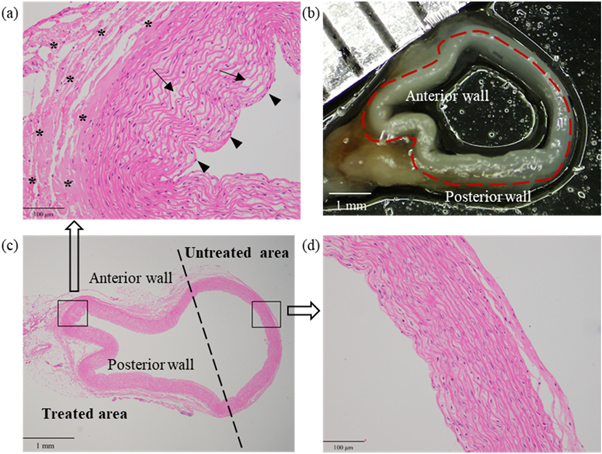

Figures 4(b) and (c) demonstrate that the microscope view of the post-sonication vessel was consistent with its histological section. In comparison with the vessel wall without sonication in figure 4(d), the sonicated vessel wall became thickened and multiple inward bulges (arrow heads) could be observed in figure 4(a). Besides, the elastic fibroblasts swelled with their intercellular spaces enlarged, and the cavities or microcapsules (arrows) appeared in some elastic fibroblasts. The elastic fibers degenerated in a wavy shape. Obvious hyalinization (stars) was found in the tunica adventitia.

Figure 4. H&E stains and microscope observation of one post-sonication vessel in group #7. (a) The pathological result of the treated area (200×). Cavities or microcapsules (arrows) between some elastic fibroblasts and multiple inward bulges (arrow heads). (b) The microscopic result of the whole vessel. (c) The pathological result of the whole vessel (20×). (d) The pathological result of the untreated area (200×).

Download figure:

Standard image High-resolution imageWith phantom #2 sonicated at 5.3 W, no cooling time was set and l was 4 mm. Figures 5(a) and (b) demonstrate the H&E stains of the vessel with 5 cm s−1 flow rate in group #7 and that without flow in group #9. After sonication, the vascular wall without flow was obviously thicker than that with 5 cm s−1 flow rate. The lumen area was decreased due to the thickened vessel wall. The number of cavities or microcapsules without flow was higher than that with 5 cm s−1 flow rate.

Vascular parameters

The microscope images of post-sonication sectioned vessel have shown the more obvious contraction in the anterior wall than that in the posterior wall. The pathology results have also demonstrated that the anterior walls were more inwardly concave than the posterior walls, which is in consistence with the microscope images (see figure 4). Compared with the posterior walls, the damage to the adventitial cells in the anterior wall were more serious and the vacuolization was prone to appear in the cells of the medial elastic fiber layer. Ota et al (2009) have found the similar vacuolization or even spongiosis in the cells in the post-sonication areas. After sonication, the venous lumen was obviously reduced due to coagulative type necrosis and loss of elastic fibers in the adventitia, and marked edema and constriction of the media (Henderson et al 2010). Besides, the substantial thickening was observed in the sonicated venous wall (Pichardo et al 2006). In this study, the temperatures were measured within the lesion and then obtained through the fitting. Tables S5–S11 demonstrate that the post-sonication temperatures on the anterior wall were much higher than those on the posterior wall. Although they were not the actual peak temperature on both vessel walls, they could explain some pathological results (figures S3 and S4). Therefore, the wall temperature is one vital factor affecting the vascular contraction.